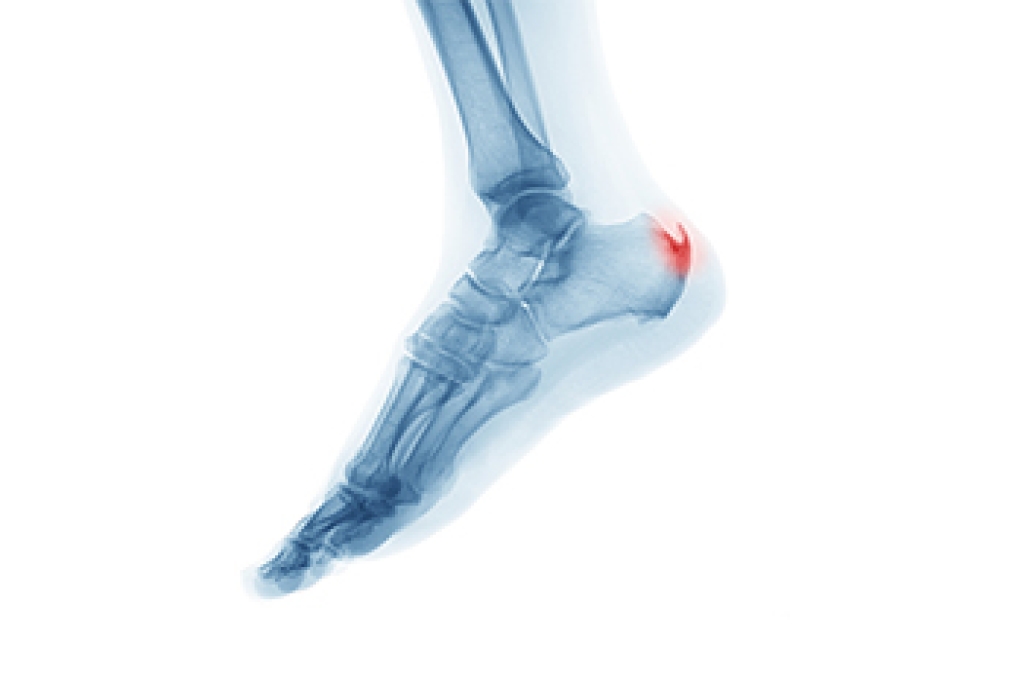

A heel spur is a bony growth that develops on the underside of the heel, often associated with inflammation of the foot muscles and ligaments. It commonly forms over time due to repetitive stress and strain on the plantar fascia, the strong band of tissue running from the heels to the toes. Symptoms include heel pain that may feel sharp or aching and is often worse after periods of rest or when first standing. Risk factors include high impact activities, sudden increases in exercise intensity, wearing improper footwear, and prolonged standing. Without proper care, discomfort may persist and affect mobility. A podiatrist can help by diagnosing the condition, reducing inflammation, and recommending supportive treatments. If you have heel pain and it has become difficult to complete daily activities, it is suggested that you consult a podiatrist who can guide you toward effective relief solutions.

Heel spurs are formed by calcium deposits on the back of the foot where the heel is. This can also be caused by small fragments of bone breaking off one section of the foot, attaching onto the back of the foot. Heel spurs can also be bone growth on the back of the foot and may grow in the direction of the arch of the foot.